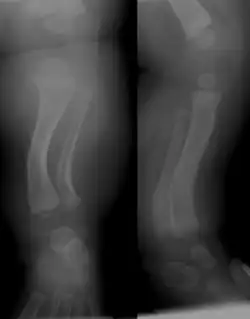

Die sehr seltene angeborene Tibia recurvata (lat. Crus valgum et recurvatum, engl. Posterior medial bowing of the tibia) stellt eine seltene Fehlstellung des Unterschenkels dar mit Rekurvation und Valgusstellung.

Leitsymptom ist die Rekurvation mit Valgusdeviation und (fakultativer) Beinverkürzung des Unterschenkels, die Diagnose wird mittels Röntgenbild gestellt. Der Verlauf mit spontaner Ausgradung bestätigt die Diagnose.